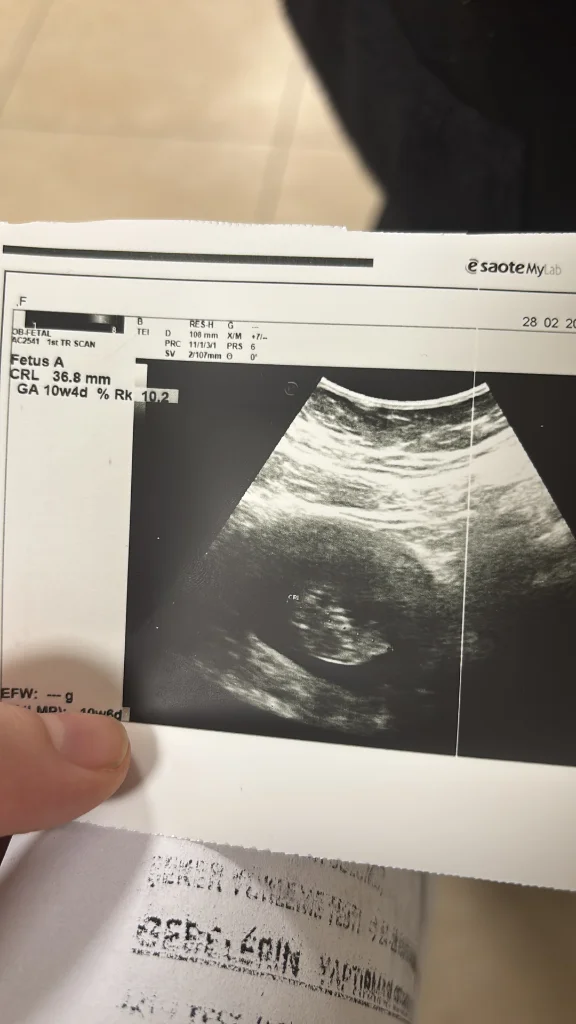

E Emooo25 Yeni Üye Anneler Kulübü Kayıtlı Üye 7 Mart 2025 41 13 3 36 7 Mart 2025 Konu Sahibi Konu Sahibi xnadia99 #73 Arkadaş lütfen bana da bir tahmin yapın çok merak ediyorum Eklentiler IMG_20250307_073925.webp 22,9 KB · Görüntüleme: 25